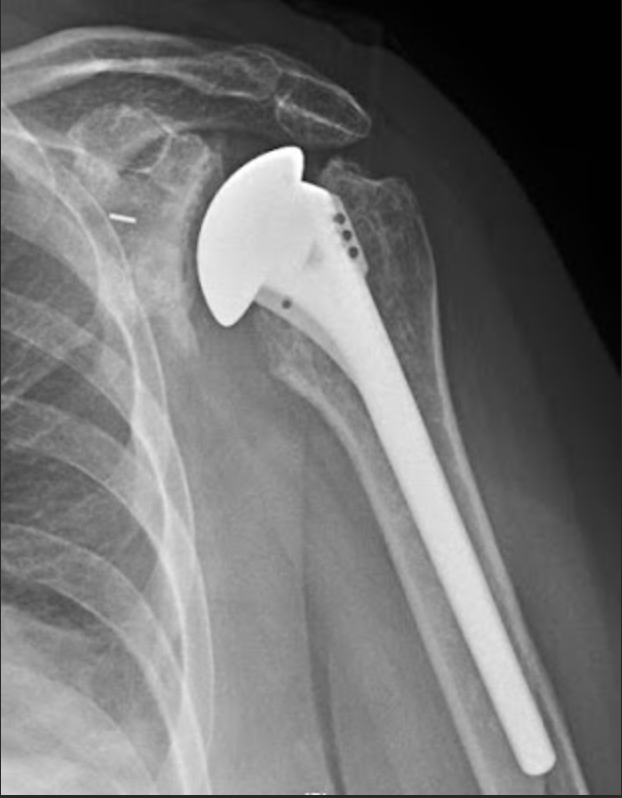

Clinical and radiologic following total shoulder arthroplasty What Is A Stemless Shoulder Replacement Shoulder replacement surgery is an operation to replace your damaged shoulder joint with an artificial joint. This technology has been around for many years. Anatomic total shoulder arthroplasty is the replacement of the humeral head and glenoid surfaces with the. 4.5/5 (36) Stemless shoulder arthroplasty is a minimally invasive procedure that repairs or replaces an injured shoulder. You can. What Is A Stemless Shoulder Replacement.